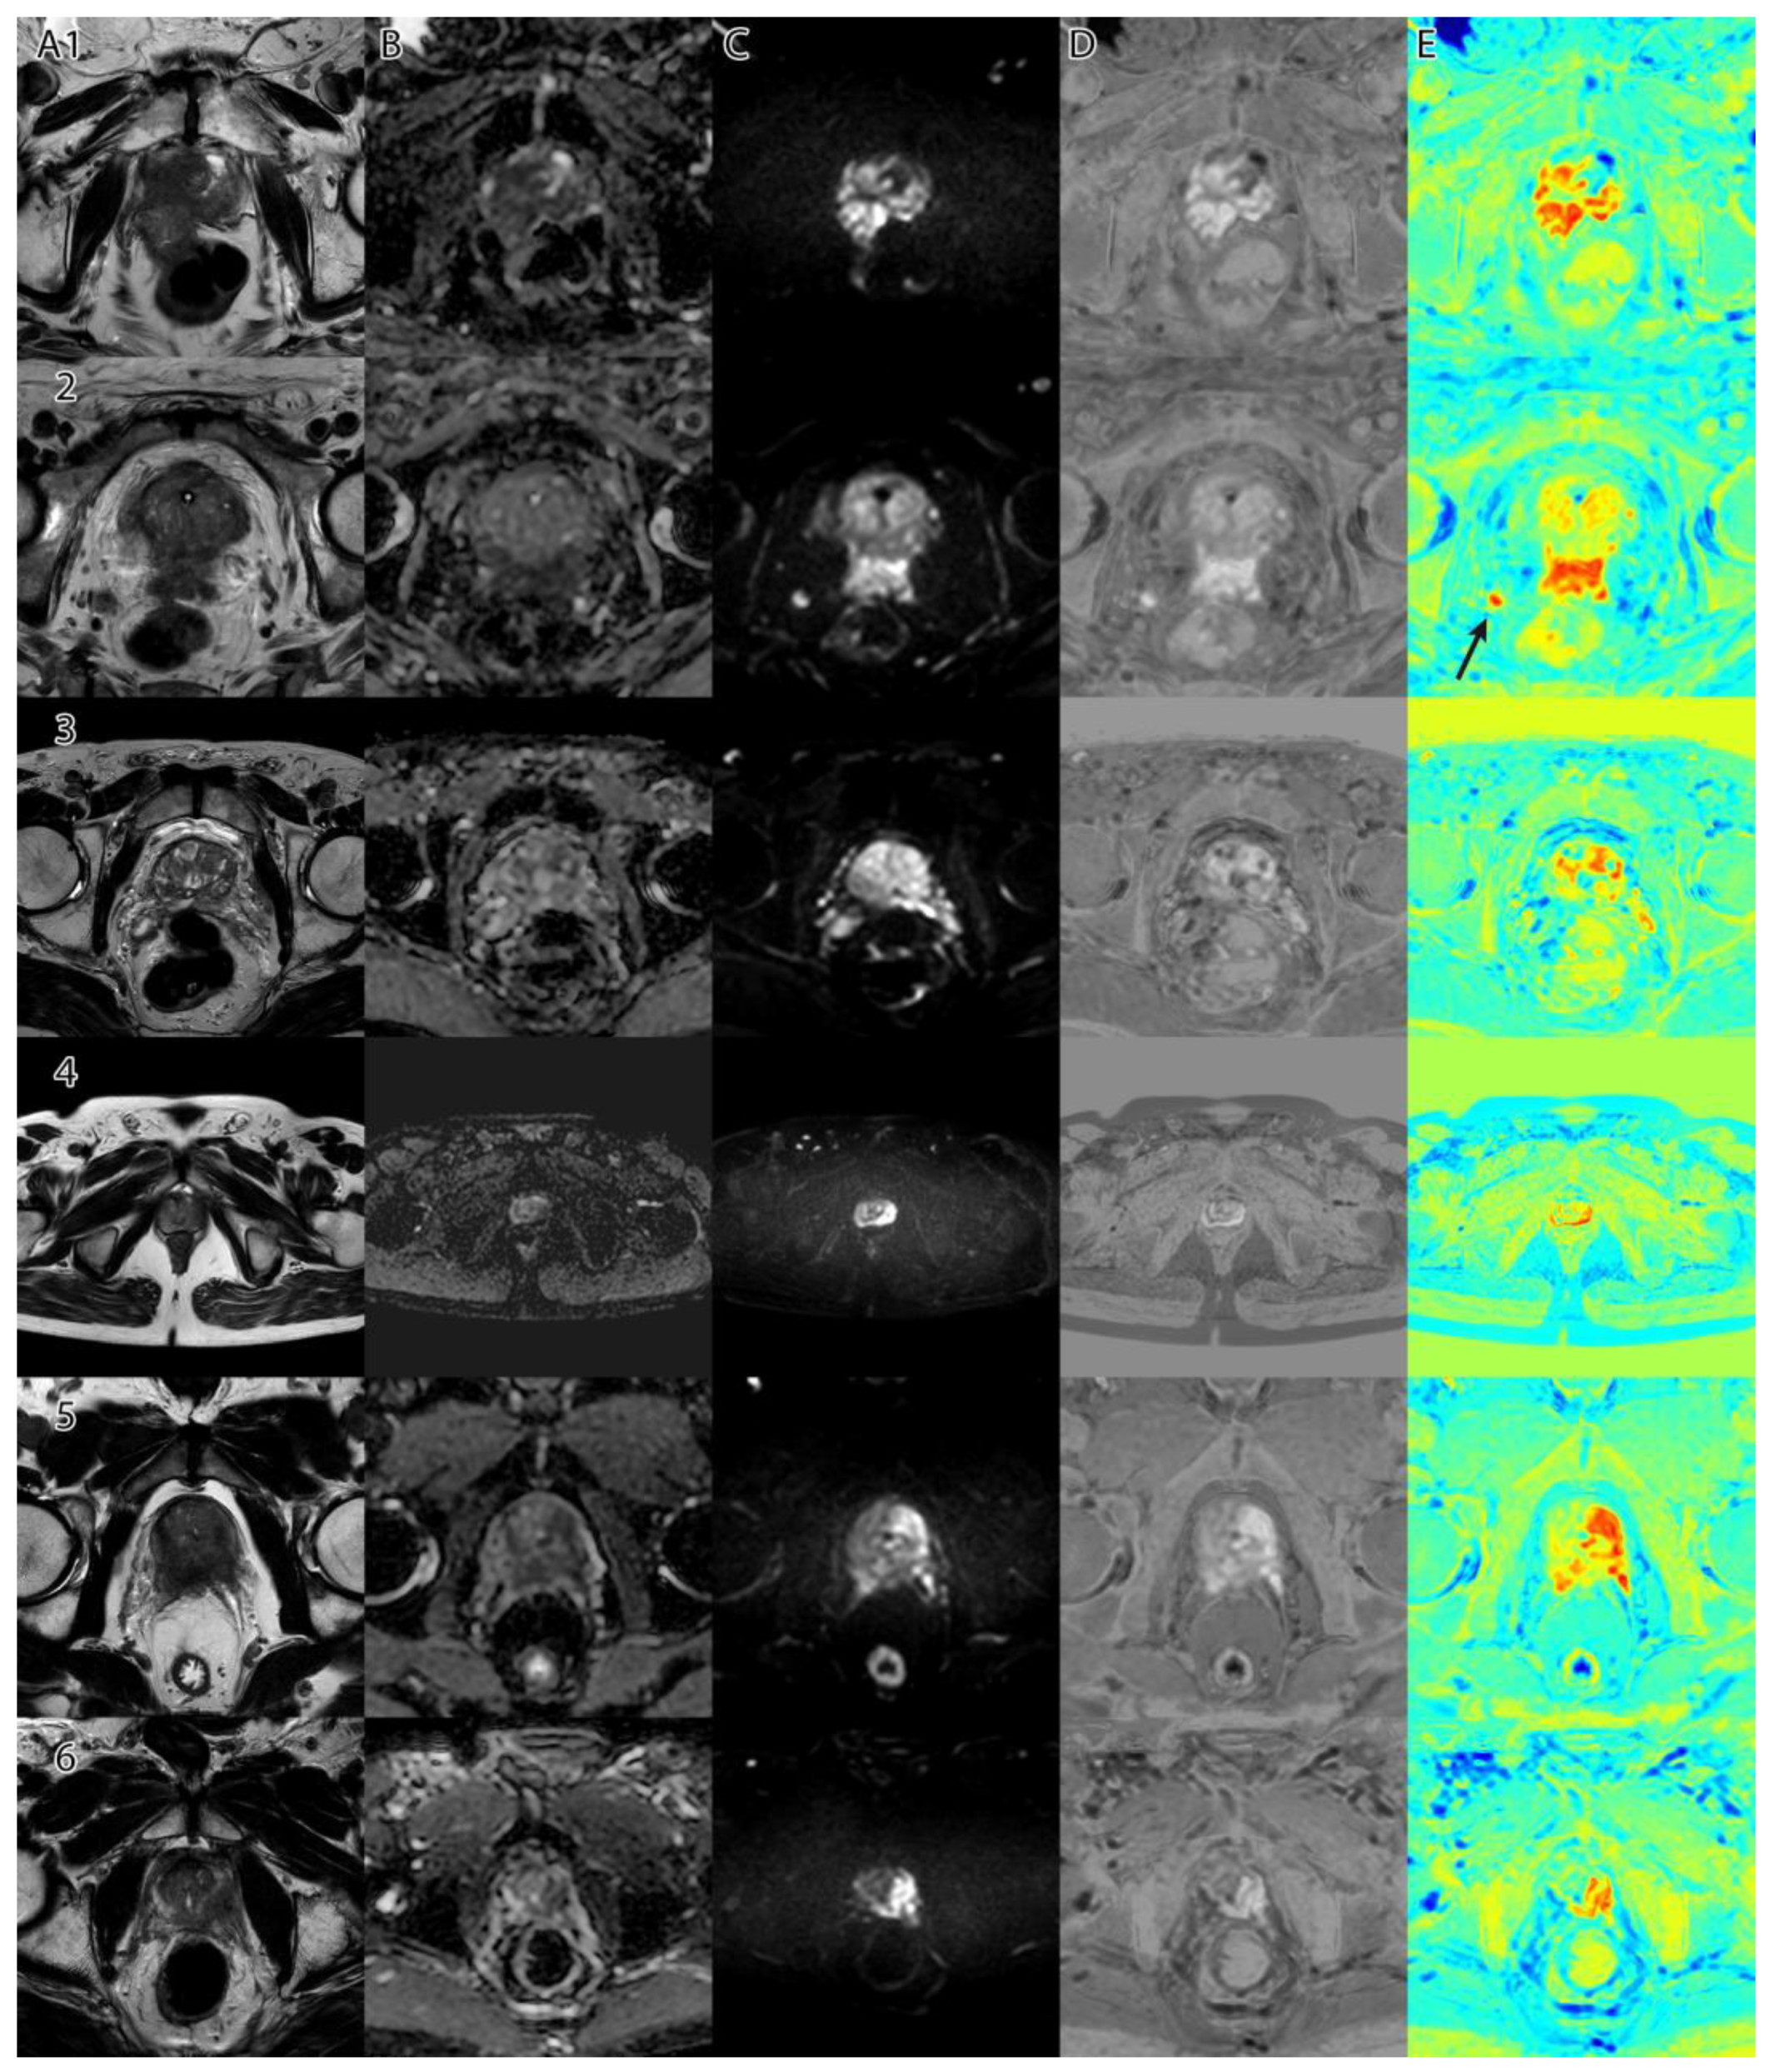

Figure 6 shows a collage of several cases and the resulting tumor intensity mask. The overlap between the PI-RADS class intervals and the original dataset can be seen in Figure 7. Using the empirically selected thresholds, we obtained 100 percent accuracy in identifying the PI-RADS 5 class on the images.

As seen in Figure 6, column D, when adding a ‘jet’ color map to the algorithm’s tumor intensity output, the highlighted zones appear in red and orange, while the less suspicious zones are colored in yellow. Non-tumoral surrounding tissue has colors ranging from green to blue.

As seen in Figure 6, image E2, the method is consistent and identifies high-risk lesions outside the prostatic area (see right side nodule in red (arrow)). The nodule was later confirmed through biopsy to be high-grade tumor prostate adenocarcinoma invasion.

Figure 6. Collage of several cases and the resulting tumor intensity mask: (column A)—T2WI; (column B)—ADC; (column C)—DWI; (column D)—tumor intensity mask (grayscale); (column E)—tumor intensity mask with ‘jet’ color map. E2—Arrow shows a high risk of extraprostatic invasion of nodules.